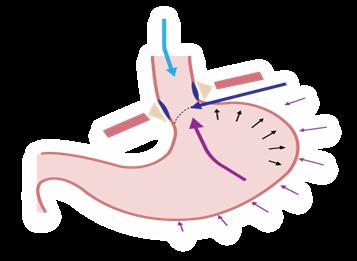

Mayor frecuencia de relajaciones transitorias del esfínter esofágico inferior (+ importante)

Desequilibrio entre las presiones intragástrica (↑) y del esfínter esofágico inferior (↓) (ENARM 2015) Esfínter esofágico corto (< 2 cm) o hipotónico (< 10 mmHg)

Anomalías anatómicas de la unión gastroesofágica (Hernia de hiato tipo I) (ENARM 2006)

Figura 1. Las relajaciones transitorias del esfínter esofágico inferior es el principal mecanismo para la ERGE Figura 2. Hernia del hiato tipo I (deslizamiento) se asocia a ERGE (ENARM 2006), y la hernia del hiato tipo II (paraesofágica) se asocia a vólvulo gástrico.